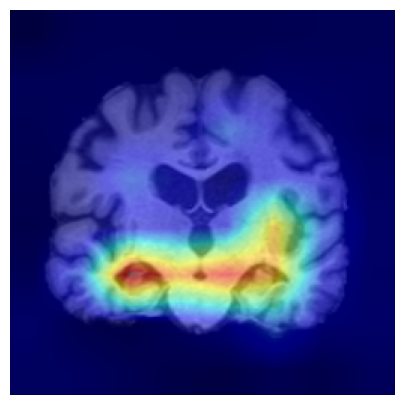

We consider two groups constructed from the ADNI dataset based on hippocampal volume, a well-established neuroimaging biomarker of Alzheimer’s disease–related neurodegeneration. Each group includes 918 2D slices. Subjects exhibiting reduced hippocampal volume indicative of hippocampal atrophy are assigned to Group 1, while subjects with preserved hippocampal volume form Group 2. This stratification induces group differences associated with disease-relevant anatomical variation and provides a clinically meaningful setting for evaluating whether the proposed feature-level explanations highlight brain regions known to be implicated in Alzheimer’s disease/cognitive impairment.

We use a ResNet-50 encoder pretrained on the UK Biobank dataset, predicting the age of brains, and adapt this pretrained model using a linear probing strategy on the ADNI dataset. Specifically, we train a logistic regression layer on top of the frozen encoder to predict group membership, while keeping all encoder parameters fixed. After training, the linear head is discarded, and the frozen encoder is used to extract embeddings for two-sample testing and for generating feature-level explanations. We apply the proposed feature-level explanation method to individual MRI scans and assess whether the resulting attributions align with known disease-related neuroanatomical patterns.

Results.

Figure 7 indicates the qualitative results. Our explainability method consistently highlights the hippocampal and medial temporal lobe regions, and the resulting heatmaps show strong correspondence with areas affected by hippocampal atrophy. These results supports that the identified regions align with established AD biomarkers.